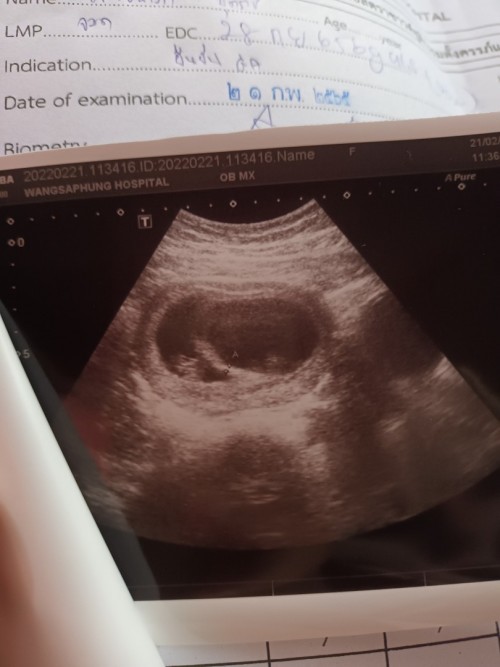

ในภาพตอน6wค่ะ ตอนนี้19+3wแล้วค่ะ😊